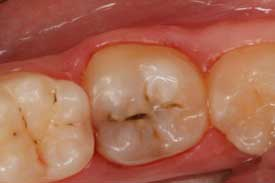

The patient presented with extensive caries on tooth No. 30 (Fig. 1). A rubber dam was placed and the decay was excavated, revealing its extension nearly to the top of the pulp chamber (Fig. 2).

Many dentists would opt to place a liner/base in a case with such a deep excavation, but this was not done in this case due to my personal comfort level with the adhesive and the fact that the patient was experiencing no sensitivity in the area even prior to treatment. The bond strengths delivered by Scotchbond Universal Adhesive when used in self-etch mode are very satisfactory, and the system’s ease of use makes it appealing when an efficient technique is desired. The technique shown here represents a simple way to create a seal over deep dentin without fear of postoperative sensitivity, and without the extra steps of placing a base.Fig. 1: Extensive caries on No. 30